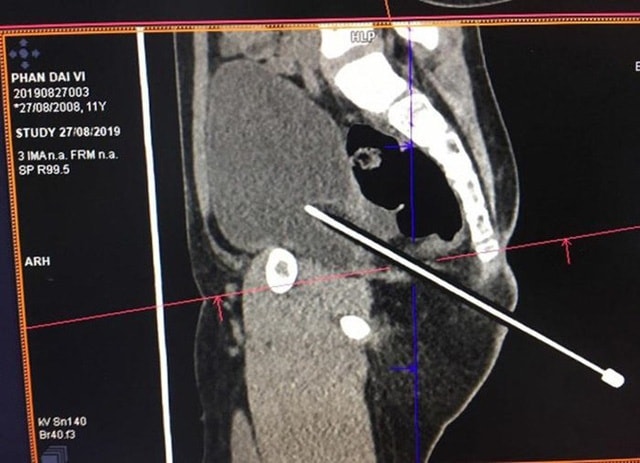

Bạn để bút chì trên ghế, bé trai 11 tuổi bị đâm thấu bụng

Bị bạn ngồi ở bàn phía sau đặt bút chì vào ghế, bé trai ngồi trúng và bị đâm thấu bụng, phải đi cấp cứu.